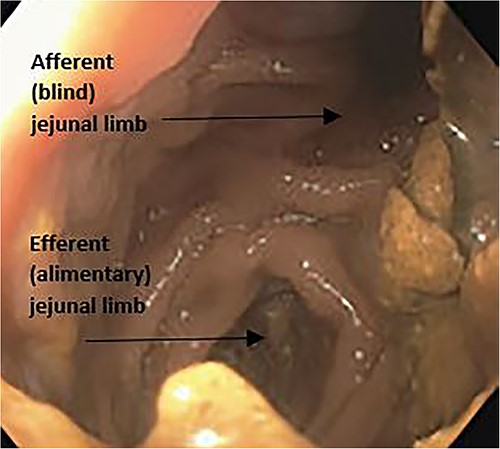

The patient was subsequently referred to gastroenterology clinic for further evaluation. An upper endoscopy was performed, which showed normal gastric bypass anatomy, aside from a blind, afferent jejunal limb measuring 9 cm, raising suspicion for CCS (Fig. 2). The rest of the endoscopic exam was unremarkable. The patient also underwent an upper gastrointestinal fluoroscopy series using barium, which confirmed filling of the long afferent limb first before entering the alimentary or Roux limb (Fig. 3). The patient reported replication of her symptoms with contrast bolus passage during the fluoroscopic exam.

Upper endoscopy image with view from gastric pouch demonstrating both the blind afferent jejunal limb and the alimentary limb.

CCS is a result of an excessively long afferent gastro-jejunal limb after a Roux-en-Y bariatric surgery (Fig. 2). The diagnosis of CCS can be challenging, as symptoms overlap with several other conditions, including bacterial overgrowth, functional gastrointestinal motility disorders and complications of gastric bypass, such as strictures or ulcers [4, 7, 8].